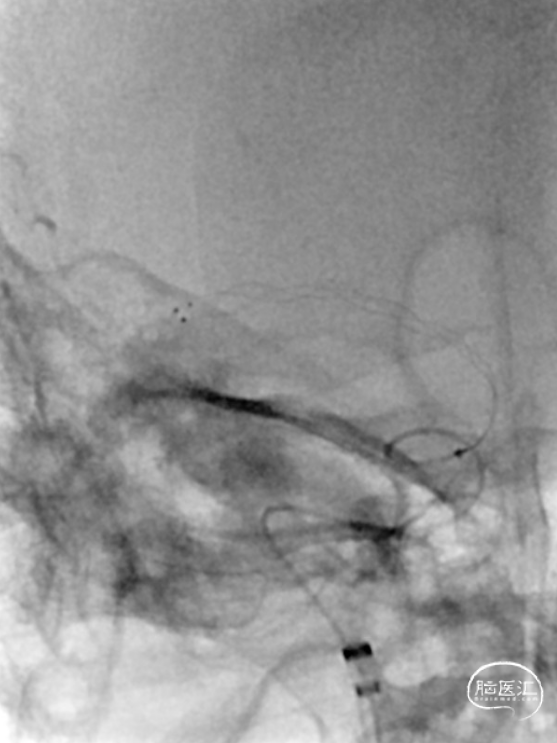

患者血管路径迂曲,经Simon2导管采用交换技术将8F导引导管内衬多功能导管,反复尝试均无法进入RCCA,后更换为Super Stiff导丝支撑,将8F导引导管送至RCCA远端。

将Catalyst7 132中间导管经导引导管送至于RICA C1段起始部闭塞处,采用ADAPT技术自C1段至C4段反复抽吸取栓,取出大量暗红色血栓。

手推冒烟见RICA C1-C5段显影,C5段以远闭塞。将Pro-18微导管在Synchro(0.014×200mm)微导丝引导下送至RMCA M2段,微导管冒烟示远端血流通畅。将Trevo XP(4×20mm)取栓支架于M1段远端向RICA末端释放,采用SWIM技术取栓1次,并同时将中间导管送至颈内动脉末端抽吸。抽出数枚暗红色血栓。

造影见RICA再通,RMCA M1段近端重度狭窄,约90%。

观察10分钟后,狭窄较前加重,局部不规则充盈缺损。术中即刻DynaCT未见造影剂染色。